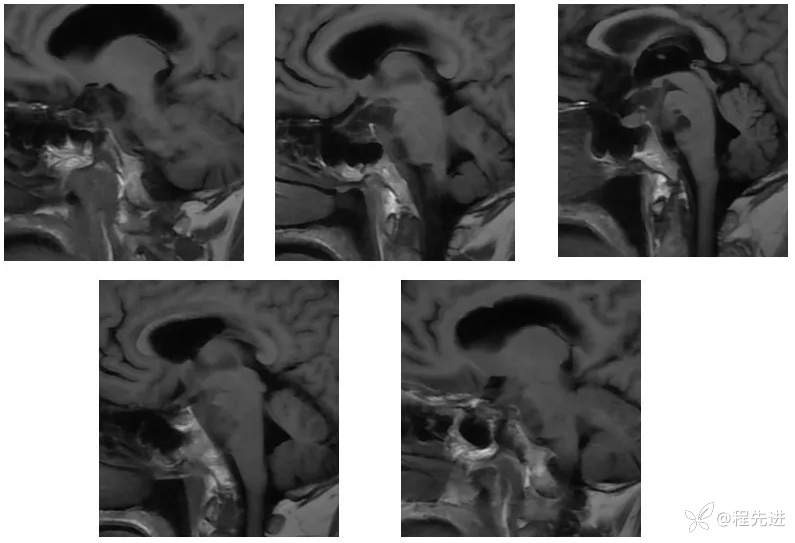

【现病史及既往史】:右眼斜视及视力下降7个月,右眼脸下垂3个月,右眼失明1个月

查体:生命体征平稳,右眼脸下垂,右眼失明,左眼内收位,外展受限,光反应迟钝,左侧角膜反射减弱,左侧听力下降,左面部痛温觉减弱无吞咽困难,无饮食饮水呛咳,伸舌舌尖左偏。